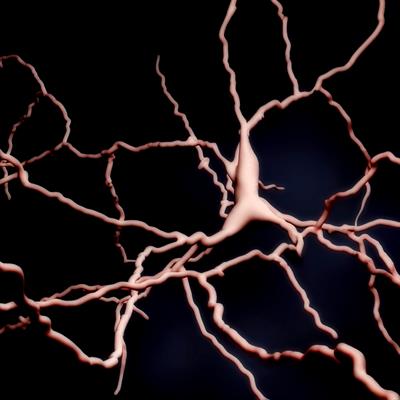

Metal Elements in Neurodegenerative Diseases

- Jian Wang

- Zang Weidong

- Yuchuan Ding

- Marietta Zille